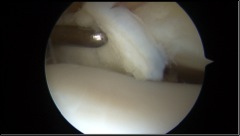

Nei casi più importanti, dove le lesioni cartilaginee sono più gravi e localizzate in zone di carico dell’astragalo, una valida soluzione è rappresentata dall’utilizzo di tecniche chirurgiche avanzate di riparazione cartilaginea che utilizzano supporti tridimensionali in grado di veicolare le cellule cartilaginee e colmare così il difetto che si è creato. Queste tecniche possono essere eseguite anche in artroscopia con maggior rispetto dell’articolazione e tempi di recupero post-operatorio di circa 3-4 mesi.